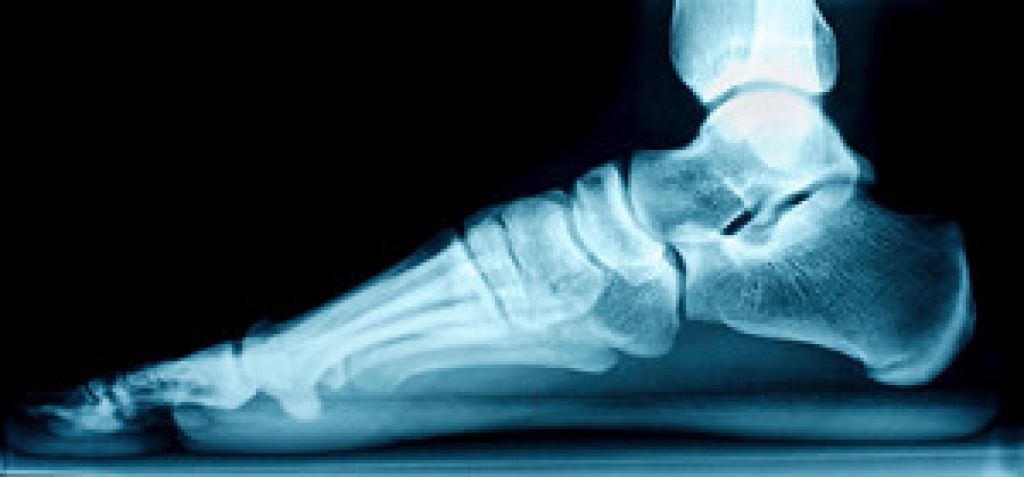

There are several nerves in the foot, and the foot condition that is known as Morton’s neuroma can indicate a nerve enlargement. A common place for this to occur is between the third and fourth toes, and nerves that have become swollen in this area may be irritated. Common symptoms patients experience with Morton’s Neuroma can include cramping, a tingling sensation in the toes, or a stabbing pain in the overall foot. This painful ailment may occur from wearing shoes that are too tight, or it may develop from other foot conditions such as flat feet or high arches. Morton’s neuroma can be managed when treated by a podiatrist and it is strongly suggested that you consult with this type of doctor if you have foot pain.

Morton's neuroma is a painful foot condition that commonly affects the areas between the second and third or third and fourth toe, although other areas of the foot are also susceptible. Morton’s neuroma is caused by an inflamed nerve in the foot that is being squeezed and aggravated by surrounding bones.